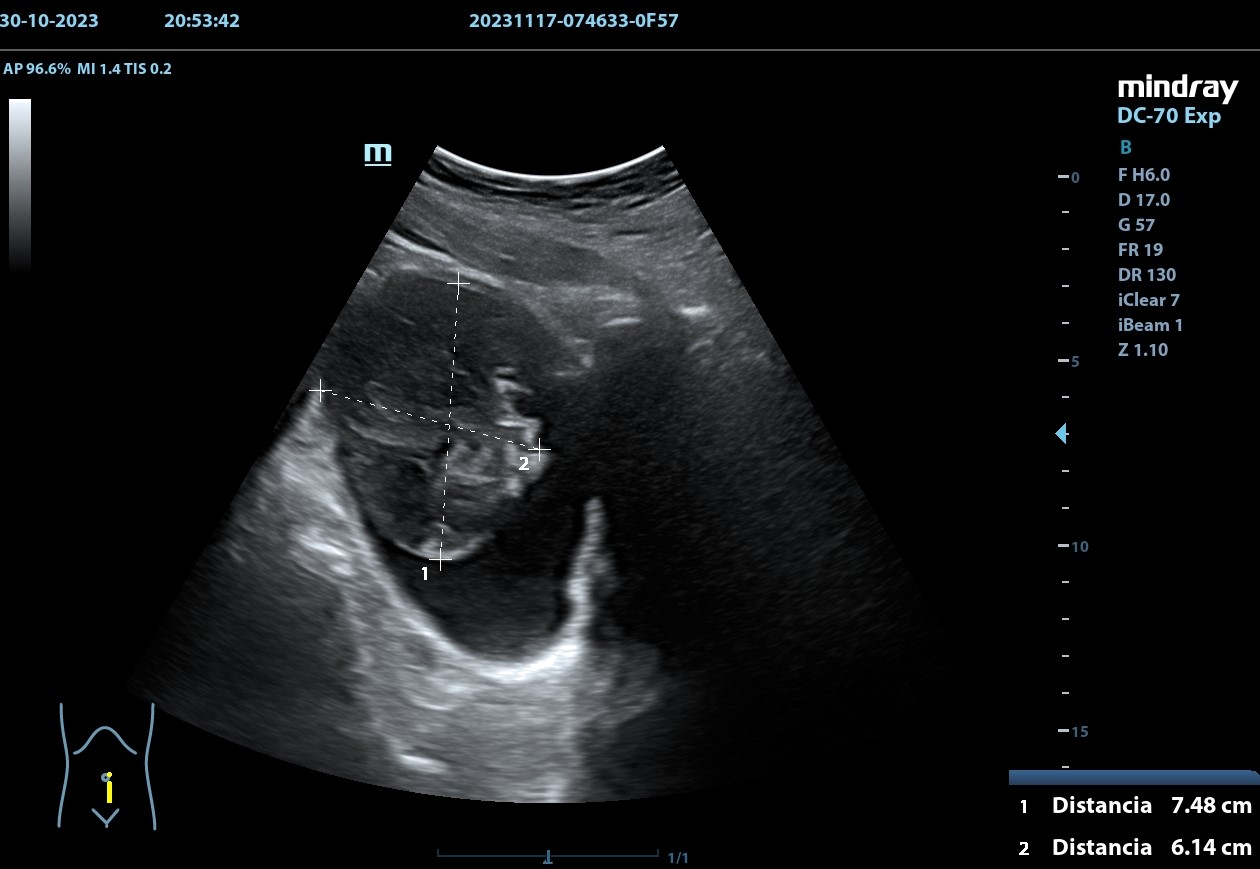

Hallazgos ecográficos

Se realiza, en consulta, una ecografía de las vías urinarias (POCUS), apreciando una lesión excrecente, pediculada, de 7,48 x 6,14 cm, que afecta a la pared izquierda y superior de la vejiga. Doppler negativo. No apreciándose jets ureterales. Riñón izquierdo de 11cm, y derecho de 9.27 cm, sin signos de dilatación de las pelvis renales que sugieran hidronefrosis.

Juicio clínico: Masa intravesical.

Diagnóstico diferencial: Tumor primario epitelial vs. tumor de origen no epitelial.